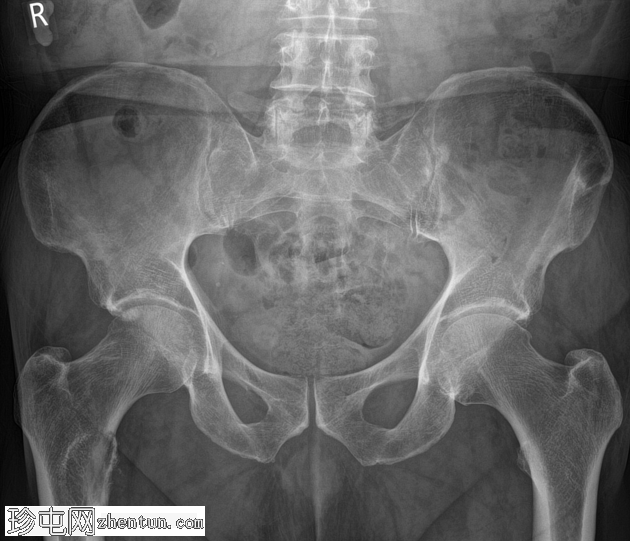

跌倒后右腿缩短且外旋。既往股骨内固定术。已知甲状腺癌伴骨转移。

X光片

正面

术前病史

右髋部疼痛加剧,负重困难。已知甲状腺癌骨转移。

右股骨近端小转子水平处出现溶骨性病变,病变呈扩张性,并伴有皮质破坏。鉴于已知甲状腺恶性肿瘤伴骨转移病史,推测为转移性病变。无病理性骨折。

建议骨科/肿瘤科诊治。